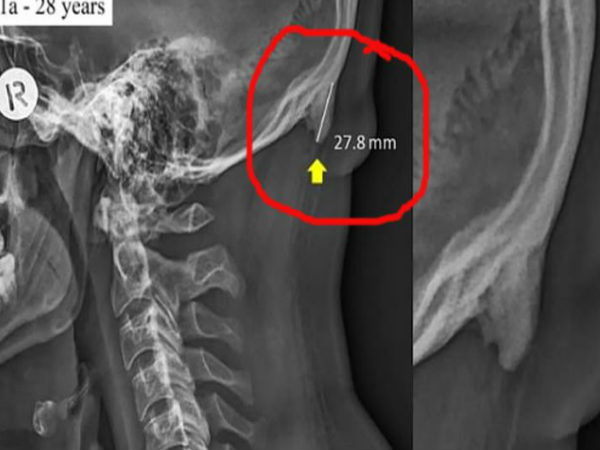

जी हां, बायोमकेनिक्स यानी कि जैव यांत्रिकी पर की गई एक नई रिसर्च में खुलासा हुआ है कि सिर को ज्यादा झुकाने के कारण युवा अपनी खोपड़ी के पीछे सींग विकसित कर रहे हैं। रिसर्चर्स के मुताबिक, मोबाइल फोन और टेबलेट्स पर अधिक समय बिताने पर सिर के पिछले हिस्से में एक अतिरिक्त नुकीली हड्डी देखी जा रही है। इसे 'टेक्स्ट नेक' का नाम दिया गया है। इसका आकार 2.6 सेमी. तक देखा गया है। मोबाइल-टेबलेट का अधिक इस्तेमाल करने वाले एक हजार से अधिक लोगों के सिर को स्कैन करने पर इसकी पुष्टि भी हुई है।

जिन लोगों में ये हड्डियां बाहर की तरफ निकल रही है, उन्हें इसका एहसास खुद हो जाता है। खास कर ऐसे लोग जो गंजे हैं, उनके सिर पर तो ये साफ-साफ बाहर से ही दिखता है। रिसर्च के समय जब डॉक्टरों ने 18 साल से 86 साल के लोगों के सिर के एक्स-रे किए तो पता चला कि ये हड्डियां 18-30 के लोगों के सिर में ज्यादा निकल रहे हैं जिसका आकार लगातार बढ़ता रह रहता है और ये कभी खत्म नहीं होता है।